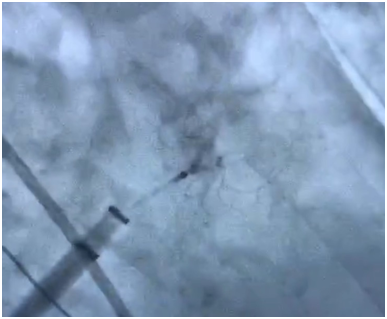

釋放左心耳封堵器